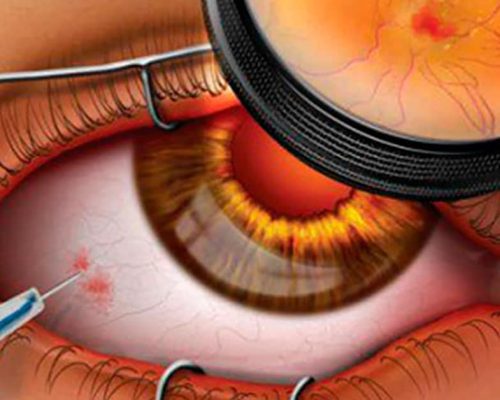

Médica Oftalmologista especialista no tratamento das doenças da retina

Mapeamento de Retina: um cuidado essencial para a saúde dos seus olhos

O mapeamento de retina é um exame fundamental para avaliar a saúde ocular de forma